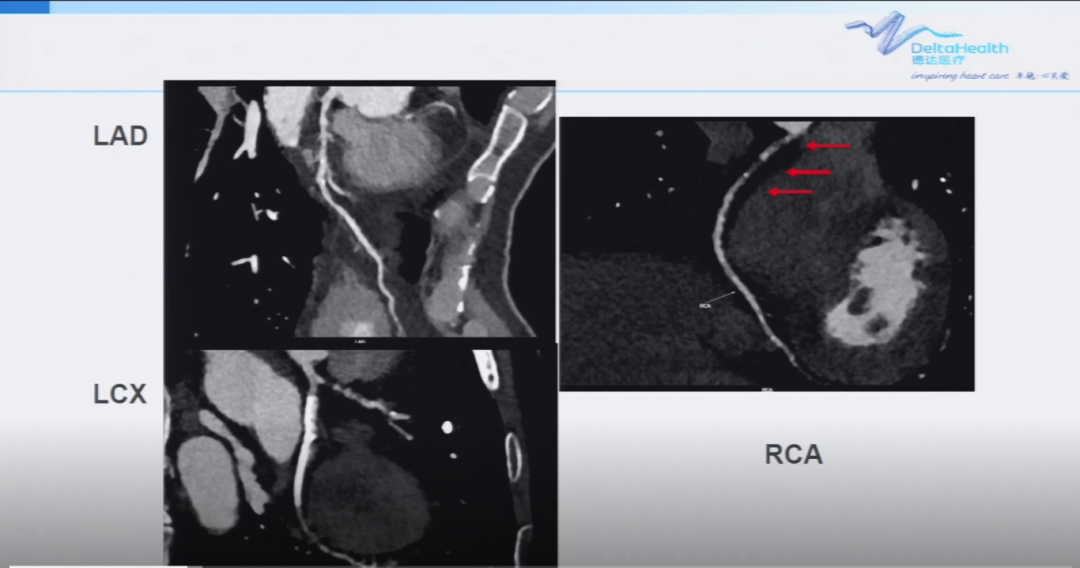

第二台手术同样也是RCA的CTO病变,该患者为84岁老年男性,主因活动后胸闷及心前区压迫感1年,加重2个月入院,既往高血压病史,术前UCG正常。外院造影提示LCX中段严重狭窄,LAD开口闭塞,严重钙化,RCA近段CTO病变,有侧枝循环。

术前造影

就开通血管的顺序,由于LAD钙化严重,处理起来相对复杂,而RCA闭塞段不是很长,葛雷教授决定此次先处理RCA的CTO病变,先尝试正向,过程中可能用到ADR技术。